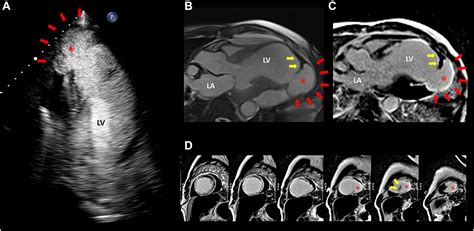

• Echocardiogram: This uses sound waves to create images of the heart, allowing doctors to visualize the aneurysm and assess its size and location.

• Cardiac Magnetic Resonance Imaging (MRI): This provides detailed images of the heart and can help in diagnosing and assessing the severity of the aneurysm.